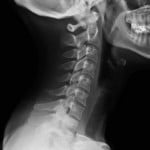

There is a common misunderstanding that xrays show broken bones. They often do, but sometimes the image may not be clear enough for the radiologist to read, or the image may be at the wrong angle or wrong site on your body to adequately see a fracture. The best example I can give of this is a client of mine about 18 years ago was in a ‘t-bone’ type accident and hurt her neck.

She went to the hospital and had an xray done on her neck. The xray did not show any fracture. About a year and a half after the accident, my client’s family doctor described her neck injury as a ‘soft tissue’ injury. We continued to monitor her condition and I encouraged her to put off any settlement discussions until she had reached maximum medical improvement. About two and a half years after the accident, without any warning/trigger, the client had a big increase in pain symptoms in her neck and went back to the hospital for another xray. This time she was given a ‘ct scan’ which is a series of xrays around her neck. These showed that she had a fractured (broken) neck. The neurosurgeon that she saw immediately after the ct scan results were known, gave the opinion that the broken neck was from the car accident.

The moral of the story is that you shouldn’t accept that you have a ‘minor’ injury, just because the xray was negative for a fracture. If you have ongoing pain, push for further investigations and further imaging.